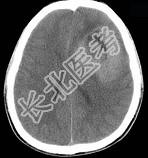

- 单项选择题男,15岁, 进行性头痛1年余,CT检查如图所示, 最可能的诊断是 ( )